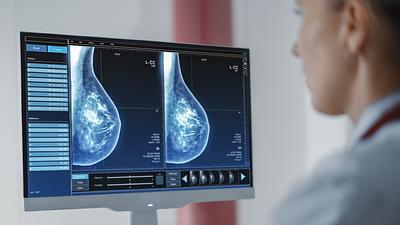

Super Centro usa IA em diagnósticos de câncer de mama

Os laudos dos exames de mamografia realizados no Centro Carioca de Diagnóstico e Tratamento por Imagem (CCDTI) são avaliados e assinados por profissionais médicos capacitados, no entanto, a IA auxilia na identificação de possíveis lesões difíceis de serem vistas.